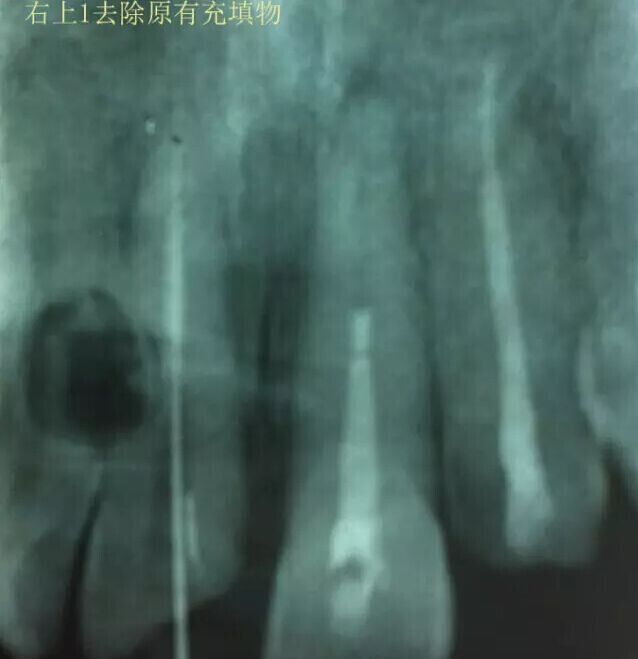

治療過程:經(jīng)患者同意。H銼去除11 21原有充填物,未發(fā)現(xiàn)明顯滲出物,無異味。K銼疏通根管,VDW根測儀測量長度,11牙20mmWL,21牙20mmWL。S3鎳鈦器械預(yù)備根管。(全程1%次氯酸鈉沖洗EDTA溶解潤滑)試尖片顯示牙膠未到位,繼續(xù)向牙根尖各2mm進入預(yù)備。吸潮紙尖吸干根管,登士柏樹脂根充糊劑輸送至根尖部位,以測量數(shù)據(jù)用牙膠尖冷充側(cè)壓充填根管,3M玻璃離子封閉根管口。不可用患牙啃咬硬物,擇日冠修復(fù)。

輔助檢查:插針X線片顯示根管內(nèi)充填物已經(jīng)取出。試尖片顯示牙膠尖未到位,繼續(xù)用K銼和機括向根尖預(yù)備。根充結(jié)束片顯示根充密實,無超充,無欠充。